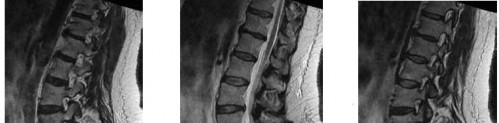

A 35-year-old male falls from a ladder and sustains an L1 burst fracture. He is neurologically intact. MRI confirms the posterior ligamentous complex (PLC) is completely intact. According to the Thoracolumbar Injury Classification and Severity (TLICS) score, what is the best initial management?

Explanation